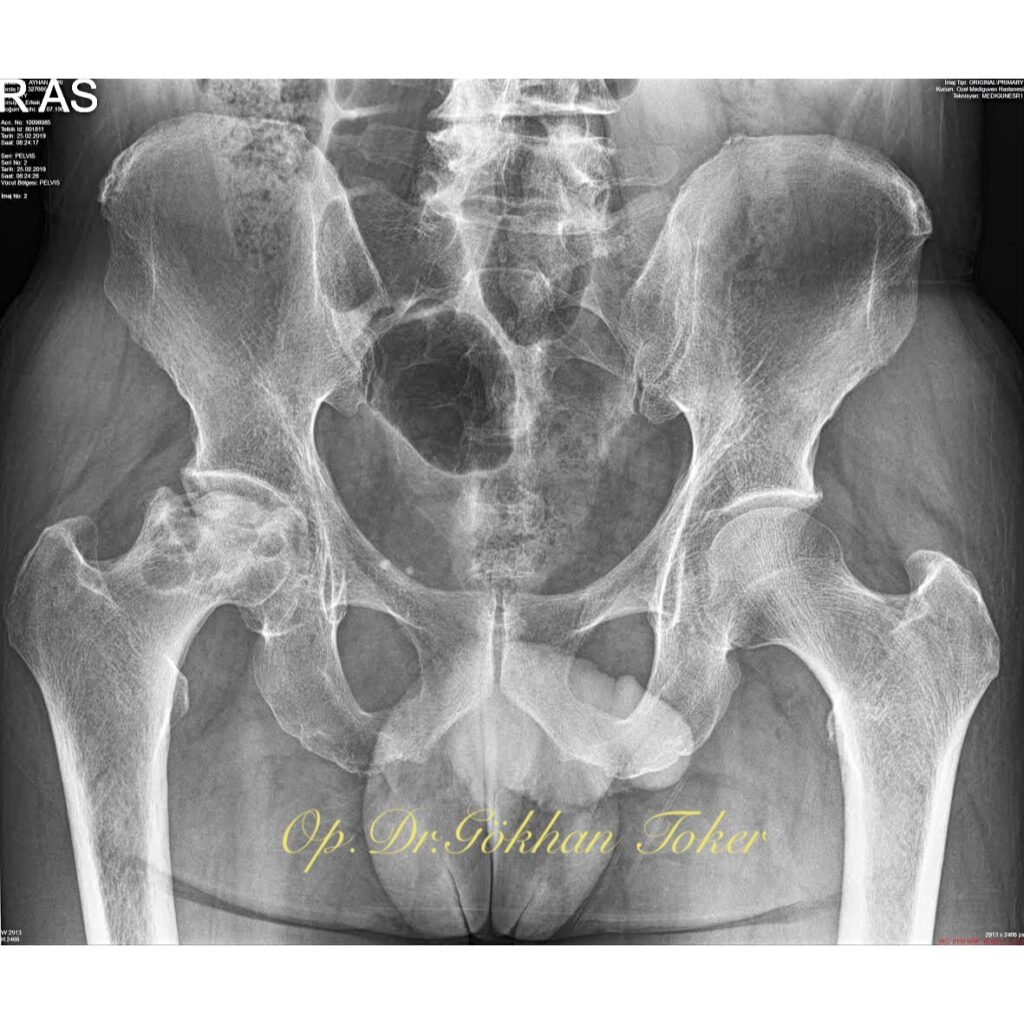

A.S.